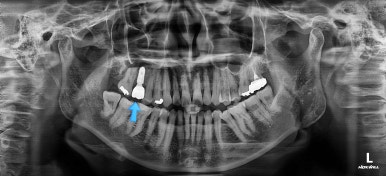

임플란트 머리 부분까지 완성이 되었어요.

교정치료와 임플란트치료를 병행해서 치아 빠진 부위가 다행히 잘 마무리가 되었네요.

부산교정치료 전후사진을 비교해 보겠습니다.

쓰러진 치아도 원위치로 만들어 기능을 회복시켜주었고, 임플란트도 1개로 마무리를 할 수 있었어요.

이렇게 단순히 임플란트를 해야 하는 상황도 간단한 교정치료와 병행한다면 치아도 아끼고 임플란트도 줄이는 매우 좋은 치료가 될 수 있답니다.